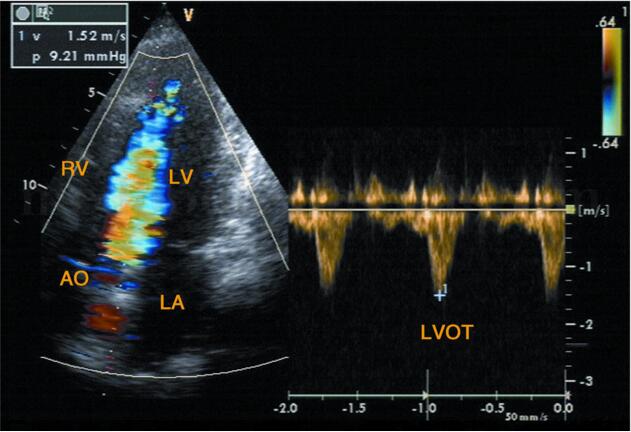

超声图片 如图2‐1‐196,图2‐1‐197。

超声描述 左房轻度增大,室间隔呈团块状明显增厚(39.7mm),左室后壁轻度增厚(11.4mm),两者之比>1.5∶1,呈非对称性;室间隔回声增粗明显不均,呈毛玻璃样改变;二尖瓣水平M型见二尖瓣前叶EF斜率下降,E峰与室间隔相碰,SAM现象(+);左室流出道狭窄,其内收缩期充满花彩血流束,射流流速3.56m/s,压差50.7mmHg。

超声诊断 肥厚型梗阻性心肌病。

3﹒彩色多普勒超声

(1)左室流出道梗阻者:收缩早期左室流出道内充满五彩细窄血流束,向主动脉瓣及瓣上延伸,狭窄越重,色彩混叠越严重。彩色血流最窄的部位即为左室流出道梗阻部位(图2‐1‐207)。

(2)非梗阻者:左室流出道收缩期充满蓝色血流(图2‐1‐208)。

(3)非梗阻者:左室流出道血流速度正常(图2‐1‐211)。